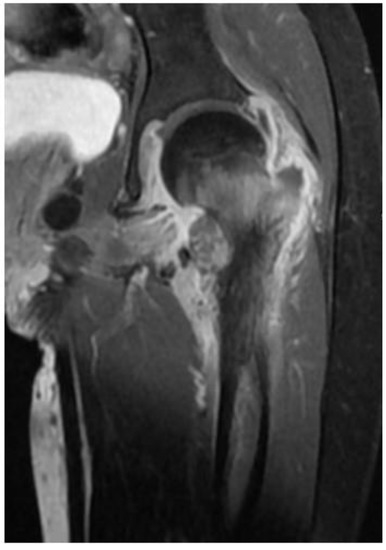

| Index case | 12Y/F | Healthy child | Chronic osteomyelitis | Tissue culture | P. species | VRC total 6 months with surgical debridement | Resolution |